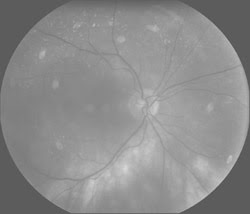

The National Cancer Institute estimated that 1,437,180 people would be diagnosed with cancer in 2008 and that 565,650 people would die of the disease. Cancer research is, of course, ongoing, and recent decades have seen great strides in our...

BioPhotonics, December 2008